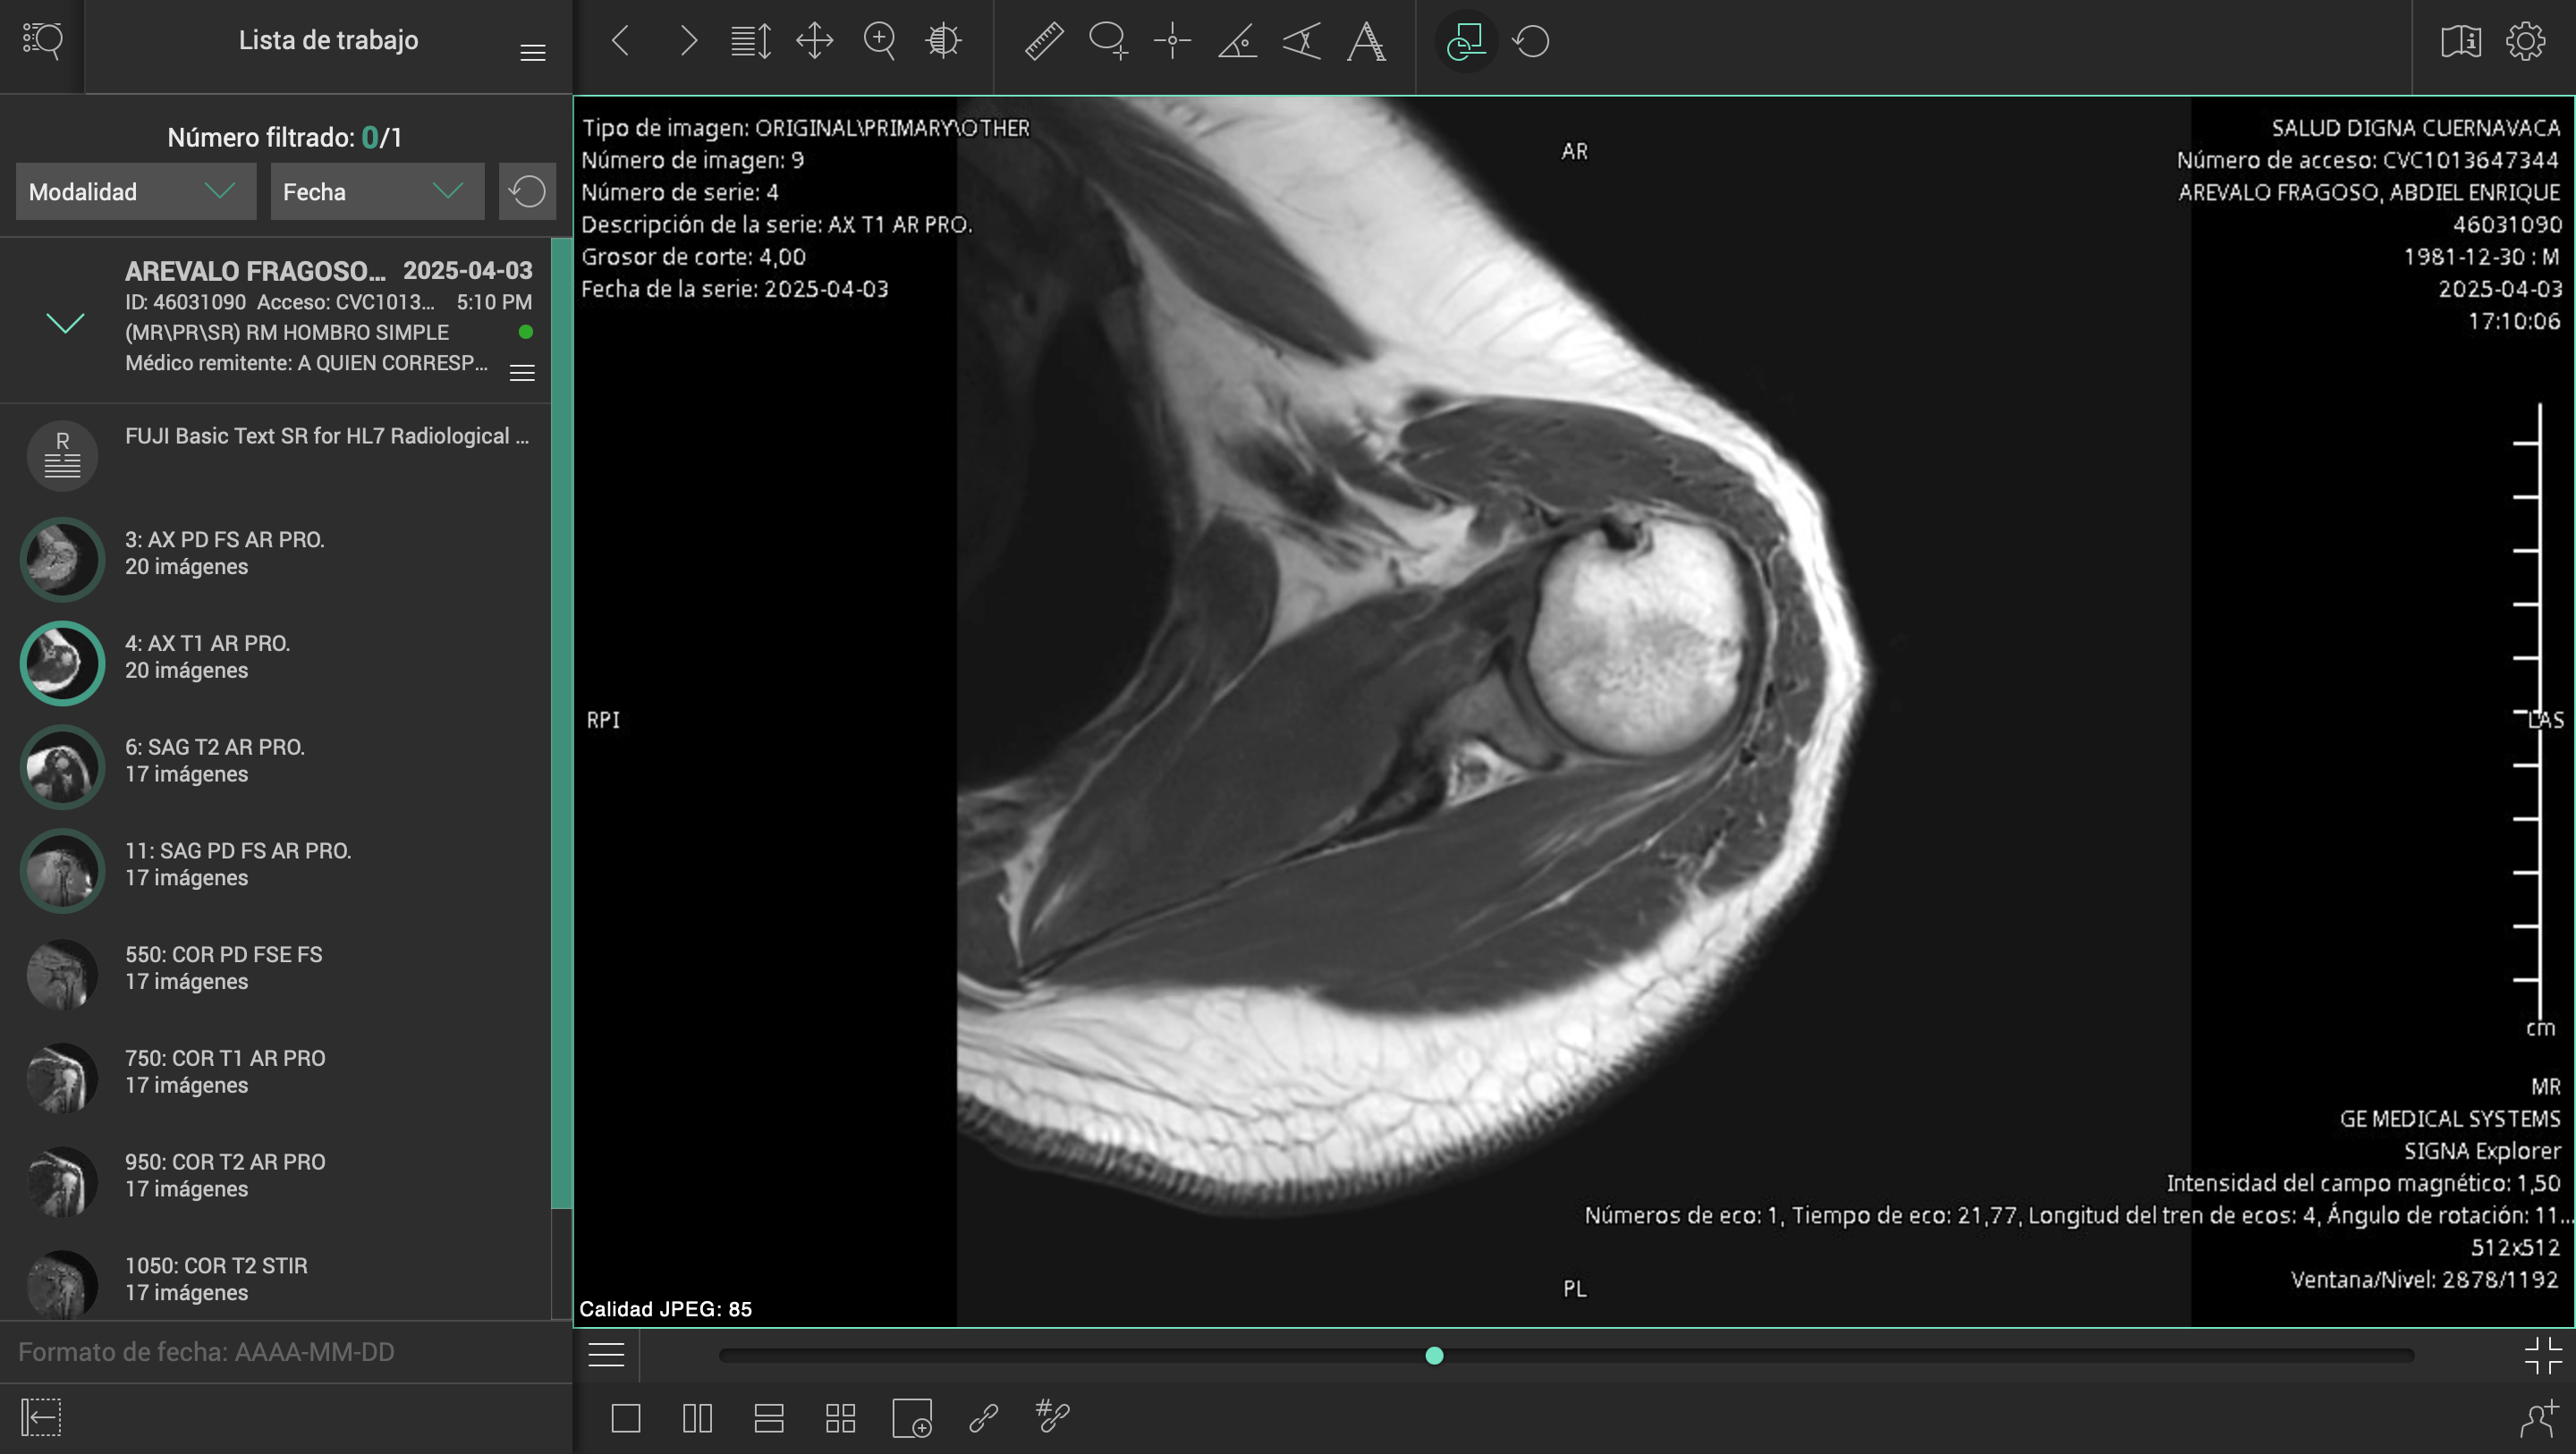

El pasado 2 de marzo de 2025, sufrí un accidente en carretera mientras conducía mi motocicleta. Un automóvil me impactó y me arrojó contra el asfalto, causándome lesiones severas en el hombro izquierdo, columna cervical y lumbar. El conductor se dio a la fuga, y hasta ahora no ha sido posible obtener justicia ni apoyo institucional.

Desde entonces, han pasado más de tres meses esperando una consulta con un especialista del ISSSTE, sin éxito. Durante este tiempo, mi salud ha empeorado, con complicaciones cada vez mayores por la falta de atención médica oportuna.

Esta situación me ha colocado en una condición muy vulnerable, médica, emocional y económicamente. Los tratamientos, terapias y cirugías necesarias superan los casi un millón de pesos mexicanos, una cifra que me resulta imposible cubrir por mi cuenta.